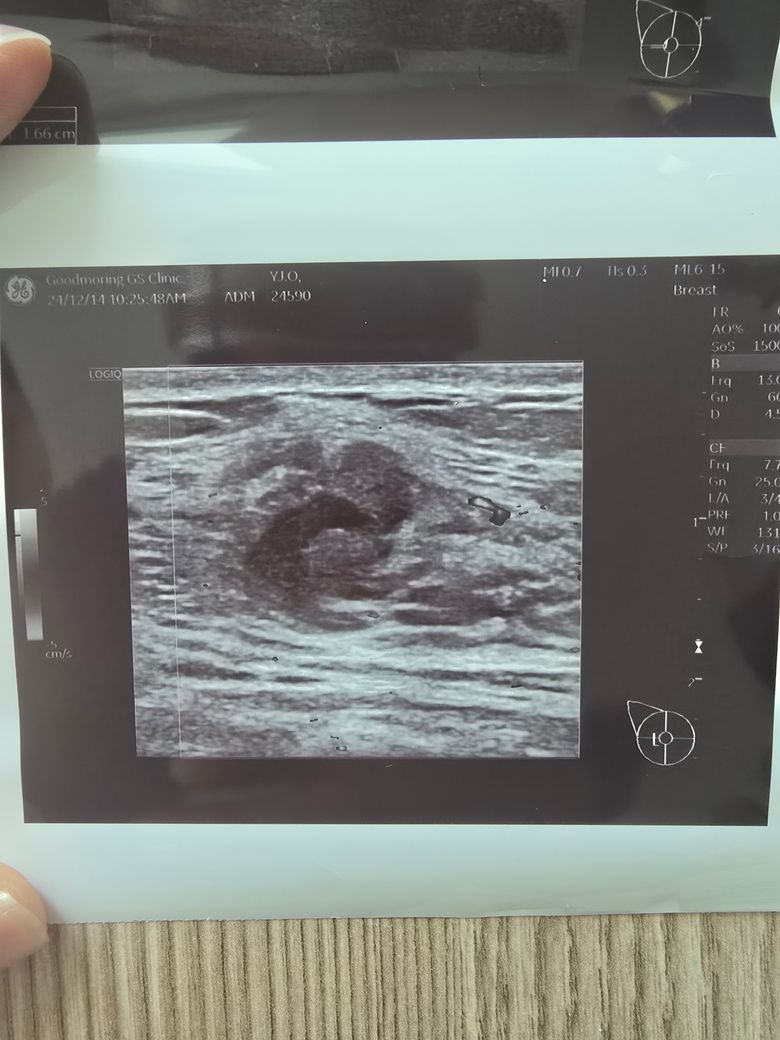

가슴부위 9시방향에 몽울잡혀 병원 방문, 초음파사진

선생님이 모양도 안좋고 림프절도 보이는것으로보아 암가능성이 많다고 조직검사하고 대학병원 알아보라고하셨는데 한편으로는 건강검진받은지 1년5개월정도 밖이 안되어서 림프절이붓는 가능성있지만 낮다고하시는데 선생님들 제발 한번만 봐주세요 부탁드립니다.

• 2번 째 사진

유방 초음파에서 관찰된 종괴의 내부 음영이 불규칙하고 주변 조직으로 침윤하는 모습이 관찰되며 림프절 비대까지 동반되어 있습니다. 이러한 상황이라면 악성 종양, 즉 유방암 가능성을 배제하기 어렵습니다.

건강검진 당시 특이사항이 없었다 하더라도, 유방암은 짧은 기간 내에도 발생할 수 있는 경우가 있어 현재의 초음파 소견과 임상증상(멍물 분비)을 더 중요하게 고려해야 합니다. 특히 종괴의 모양이 불규칙하고 경계가 분명하지 않으며 림프절 이상이 동반된다면, 조직검사를 통해 확진을 받는 것이 필수적입니다.